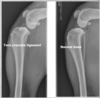

CCLR (Cranial crucial ligament rupture) on radigoraphy. (3)

Can be seen: - Compressed infrapatellar fat pad - Distal displacement of popliteal sesamoid - Osteophyte development if chronic/ time has passed since rupture. Evaluate both sides!